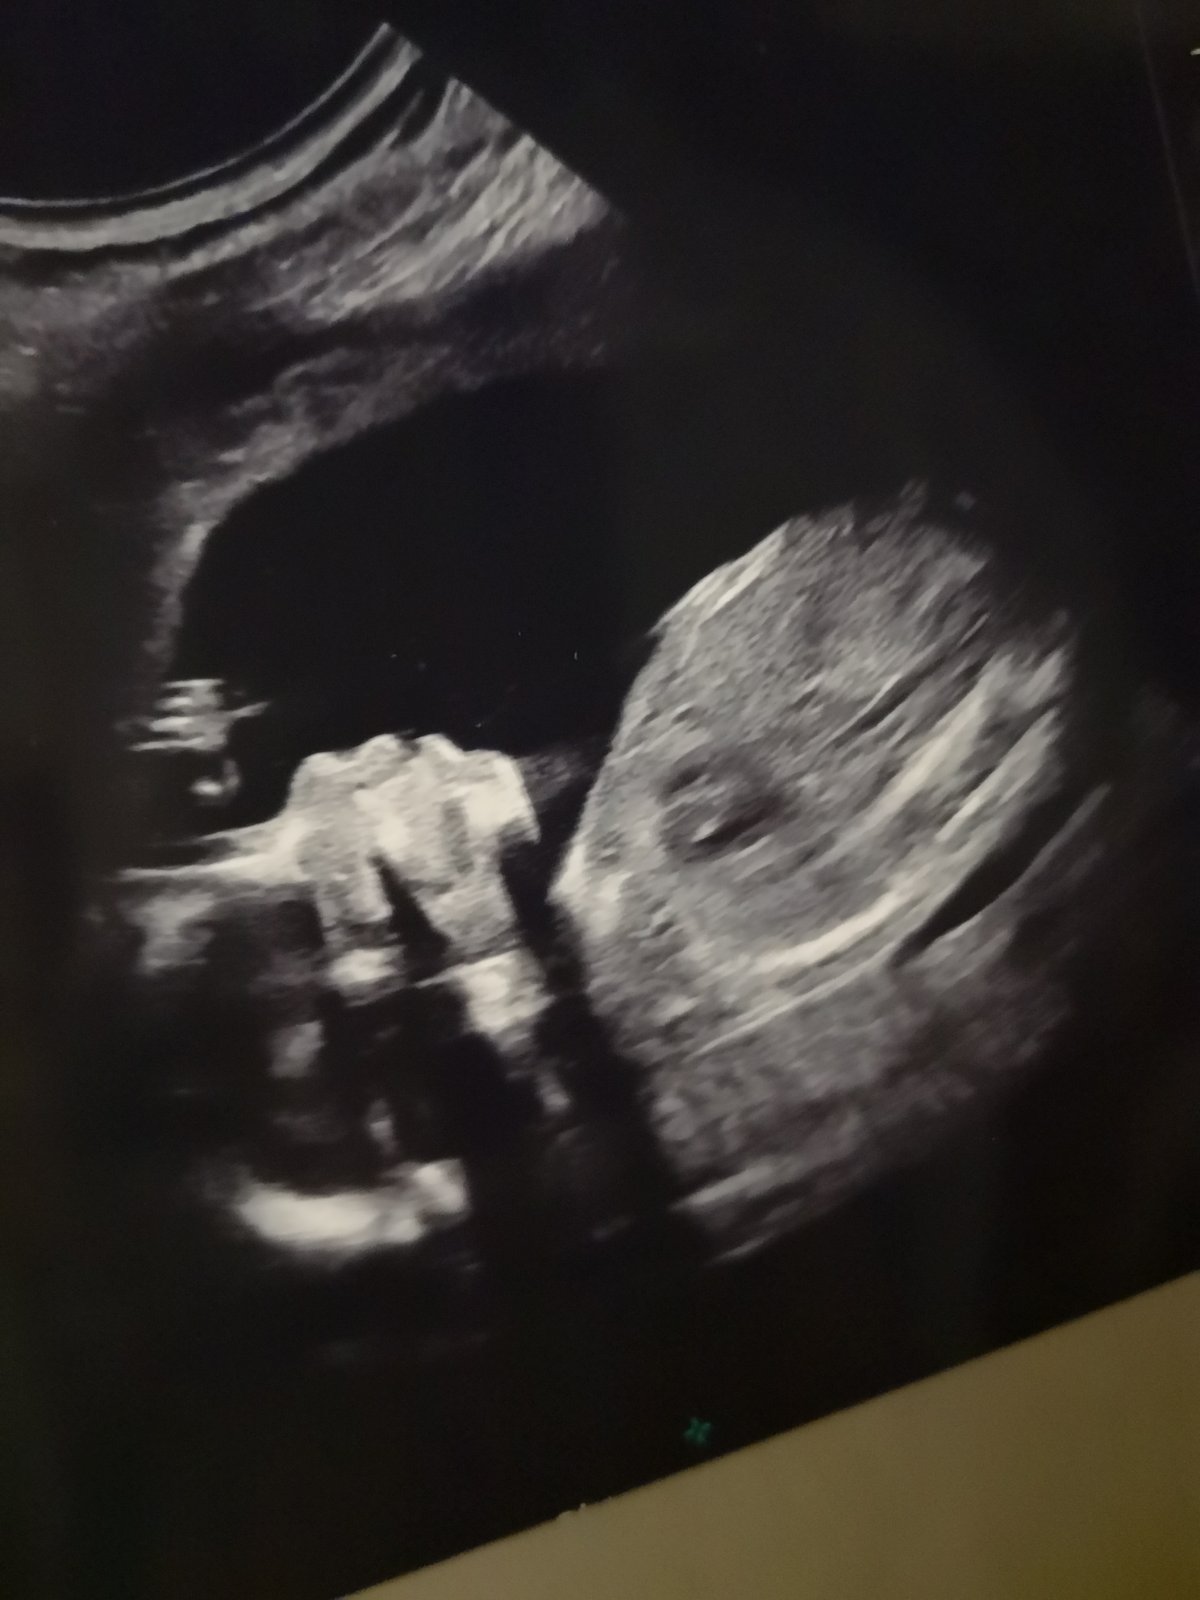

@lalusheee to je dobre ze je vse v poradku...ty deti vypadaji jako mimozemstane.take se uz tesim...nechavate si nekdo ty 3d fotky? Nikdy jsem si je neporizovala...tak nevim..

Tak 2. screening za námi a pořád nevíme, co to bude 😉 Nám je to celkem jedno, hlavně aby to bylo zdravé, ale všichni ostatní tak nějak počítají s holčičkou ;-D Jsem zvědavá, kolik růžových oblečků nám Ježíšek nadělí..... jestli to pak bude kluk, to se bude mít ;-D